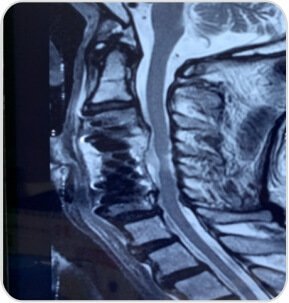

A 70 year old male presented with left upper limb radiculopathy, difficulty in walking due to imbalance with posterior column involvement and brisk reflexes and Babenski sign positive. MRI shows significant cord compression with myelomalacia changes.

Pre-op MRI showing significant cord compression